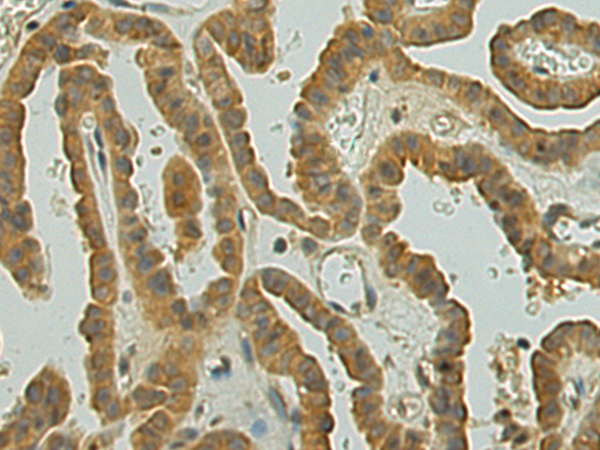

分类: 科研抗体货号: P01992别名: STAP1; ART-27应用: IHC反应种属: Human, Mouse, Rat